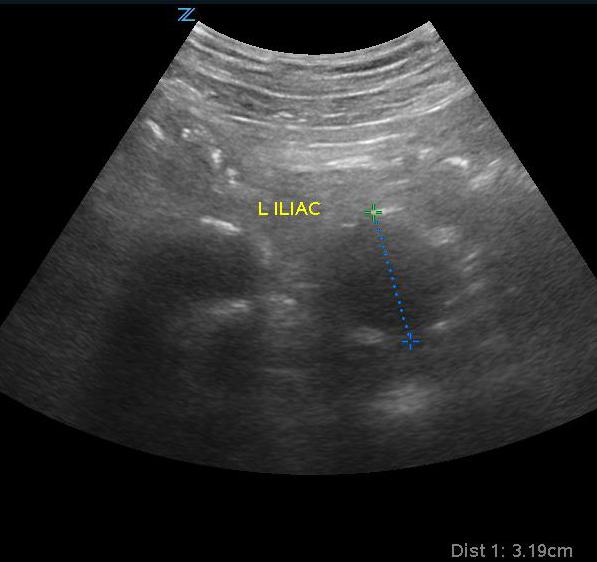

- Obtain views of the iliac arteries if possible. Normal measurements should be less than 2.0 cm.

- Iliac artery aneurysm is outside of the purview of emergency medicine and bedside ultrasound but if noted to be larger than >1.85 cm for a man and >1.5 cm for a woman, appropriate follow-up should be organized as significant risk of rupture and death are associated with isolated iliac artery aneurysm.16

- Figure 8. Iliac artery aneurysm